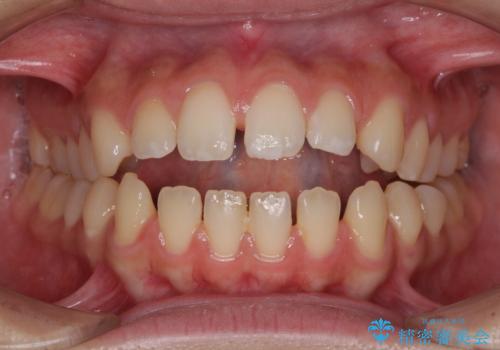

[ 前歯開咬 ] 前歯が噛んでいない マウスピース矯正治療

担当医 大元洋佑